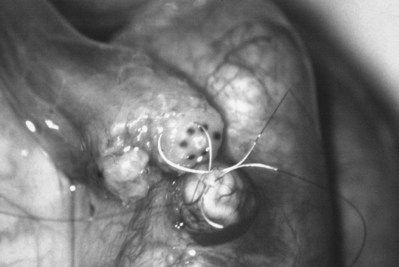

After opening the tunica vaginalis, the epididymis is inspected under the operating microscope. An anastomotic site is selected above the area of suspected obstruction, proximal to any visible sperm granulomas, where dilated epididymal tubules are clearly seen beneath the epididymal tunica (Fig. 22–29). A relatively avascular area is grasped with sharp jeweler’s forceps and the epididymal tunica tented upward. A 3- to 4-mm buttonhole is made in the tunica with microscissors to create a round opening that matches the outer diameter of the previously prepared vas deferens. The epididymal tubules are then gently dissected with a combination of sharp and blunt dissection until dilated loops of tubule are clearly exposed (Fig. 22–30). If the level of obstruction is not clearly delineated after the buttonhole opening is made in the tunic, a 70-µm diameter tapered needle from the 10-0 nylon microsuture is used to puncture the epididymal tubule beginning as distal as possible and fluid is sampled from the puncture site. When sperm are found, the puncture sites are sealed with microbipolar forceps, a new buttonhole is made in the epididymal tunic just proximally, and the tubule is prepared as described previously.

Figure 22–29 An anastomotic site is selected above the area of suspected obstruction, proximal to any visible sperm granulomas, where dilated epididymal tubules are clearly seen beneath the epididymal tunica, as marked by an arrow.